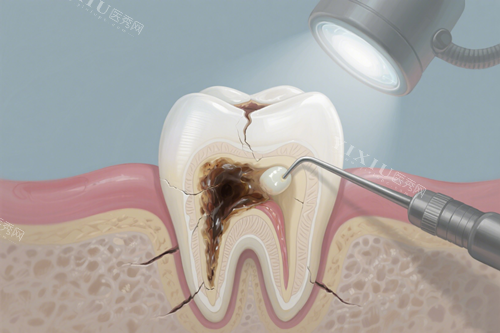

牙洞不是一天形成的,背后有多重原因。

孩子爱吃甜食是常见导火索,糖分在口腔里被细菌分解后产生酸性物质,慢慢腐蚀牙齿表面。

再加上小朋友刷牙可能马虎,食物残渣卡在牙缝里,给细菌提供了温床。

有时候,咬硬物或刷牙力度过大,会导致牙釉质受损,让牙齿更容易被蛀空。

细菌感染一旦深入牙神经,就会引发剧烈疼痛,所以日常清洁肯定不能偷懒。